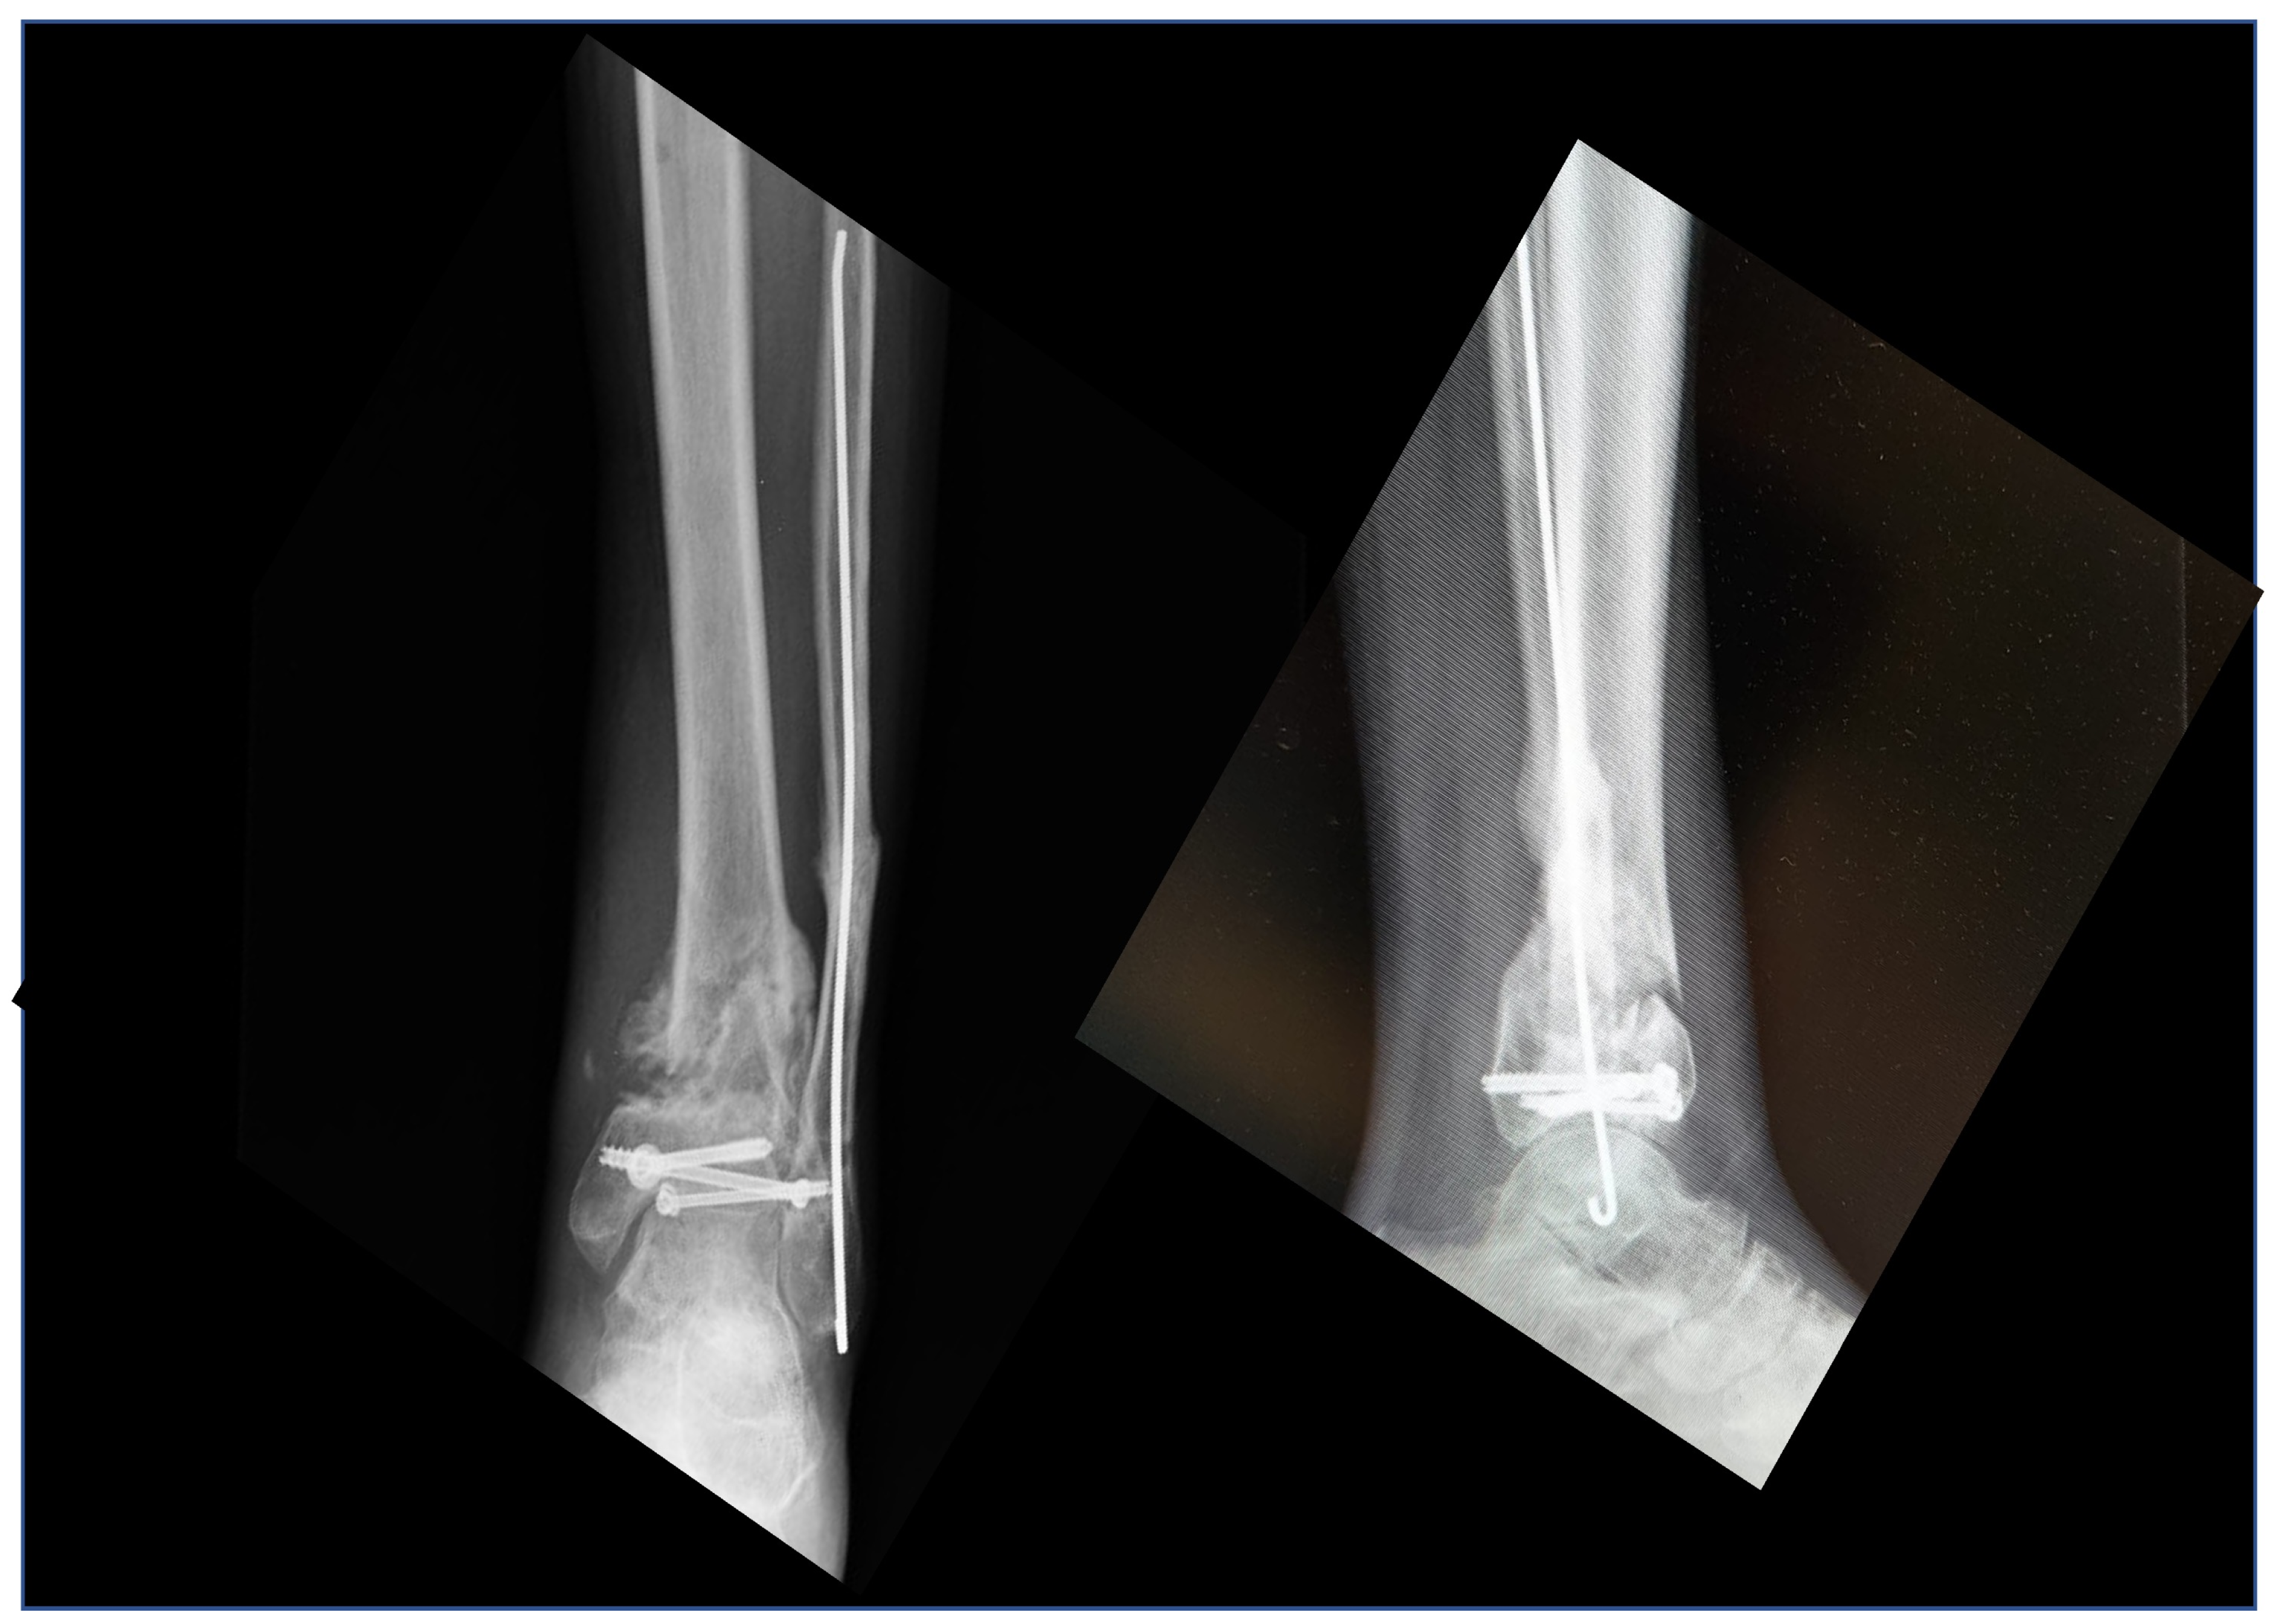

Custom-Made Implants in Ankle Bone Loss: A Retrospective Assessment of Reconstruction/Arthrodesis in Sequelae of Septic Non-Union of the Tibial Pilon

2. Materials and Methods

2.1. Planning Procedures and 3D Technology

2.2. Study Population

3. Results